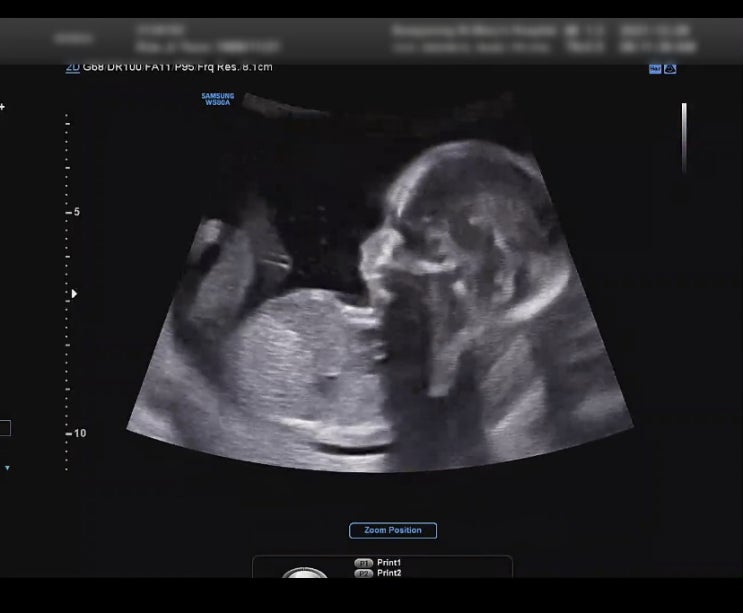

임신 21주 정밀초음파 ( 정밀초음파용어정리/배뭉침현상/입체초음파사진/은평성모병원 정밀초음파/21주배크기 )

임신 6개월 21주5일 내일이면 벌써 22주다. 17주 정도 지나니 정말 시간이 빠르게, 내 몸무게와 배크기도 ...